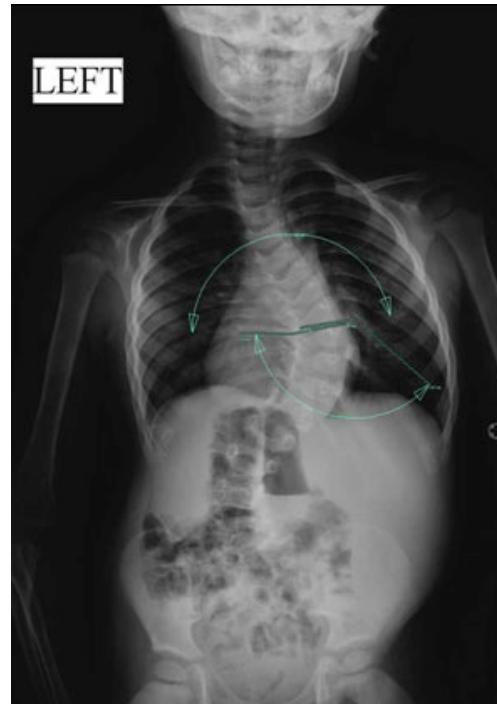

Scoliosis

Deformities

Scoliosis Classification

Adolescent Idiopathic Scoliosis

- Definition: Coronal plane spinal deformity most commonly presenting in adolescent girls from ages 10 to 18

Imaging:

Severity Grades:

- Mild: 10-25°

- Moderate: 25-45°

- Severe: >45°

Treatment Based on Severity:

- Observation: Mild curves, depending on age and skeletal maturity

- Bracing: Moderate curves (25-45°) in growing patients

- Surgery: Severe curves (>45°) or progressive curves